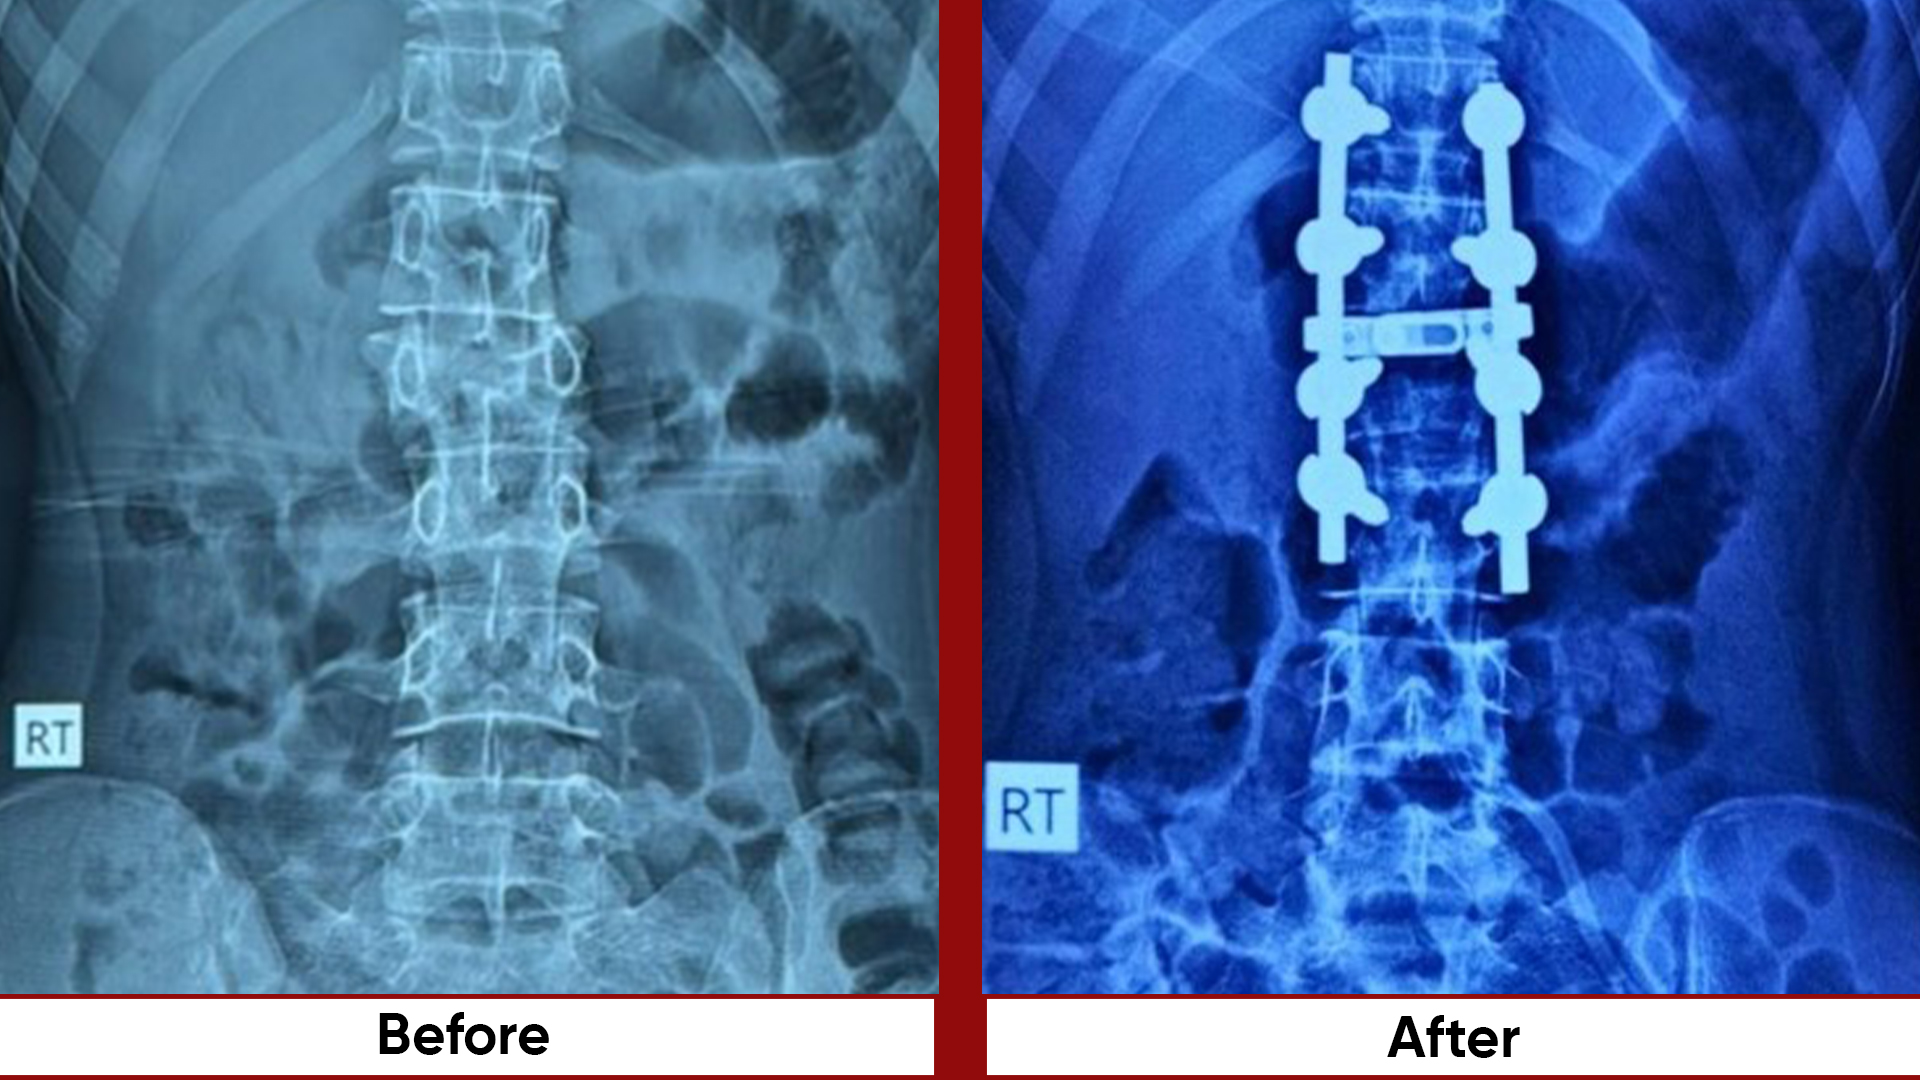

• Fracture Management (simple and complex trauma)

• Deformity Correction (limb lengthening, bowlegs, knock knees)

• Osteotomies (bone realignment surgeries)